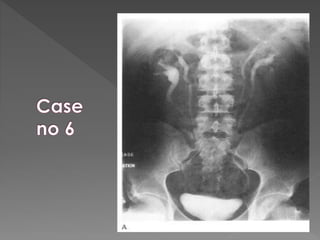

X ray films 1)Pre contrast 2) 5 mins 3) 25 mins 4) Post void